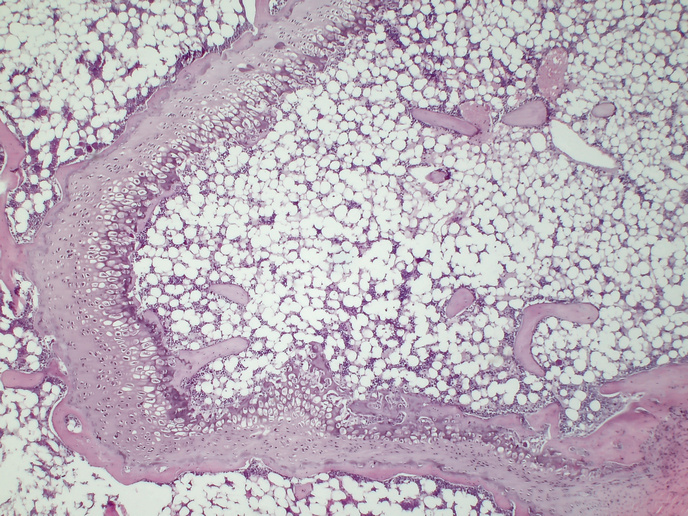

In 2022 almost 60 % of adults and nearly one in three children were overweight or obese in Europe, notes the World Health Organization(opens in new window). As the trend is showing no sign of a downturn, improving our understanding of the relationship between the changes adipose tissue undergoes in obesity, and the impact that might have on inflammation is timely. “In the last two decades we have recognised that the relationship between the functions and interactions of our immune cells and white fat cells, adipocytes, are critically important to our health,” says Eran Elinav(opens in new window), professor in the Department of Systems Immunology at the Weizmann Institute of Science(opens in new window) and director of the Microbiome and Cancer Division at the German Cancer Research Center(opens in new window) (DKFZ). Elinav, who coordinated the European Research Council(opens in new window) (ERC) supported ADIMMUNE project, explains that the precise molecular nature of such interactions, such as the types of cell subsets signalling to each other, and the nature of those signals, remain unknown in most cases. “This is due to both methodological and conceptual reasons. For example, the technology that allows us to characterise the gene expression profiles of single cells, known as single cell transcriptomics, has only recently been developed. But the process is challenged by fat cells, which have particular traits.” Even more demanding is unravelling the impact that the large communities of microbes residing within our bodies, our microbiome, have on the networks of communication between our cells, the tissue dynamics and the concomitant effect on our health. “In our project, we set out to meet all of these challenges, by functionally decoding the cell interaction networks in adipose tissue, their molecular nature and their regulation by the gut microbiome,” adds Elinav, who heads the ElinavLab(opens in new window).

The project used recently developed, high-throughput, (rapidly generated) genomic, microbiological and gnotobiotic(opens in new window) tools, in newly generated mouse models. Gnotobiotic refers to the fact that the mice models were germ-free and then colonised with specific strains of bacteria. The result being that the team was able to precisely identify which bacteria were provoking any given interaction. Their comprehensive approach also integrated an analysis of how genes of certain bacteria in the gut microbiome were functioning, using CRISPR(opens in new window), microbial culturomics(opens in new window) and in vivo metabolic analysis. For these studies, ADIMMUNE drew on human volunteers, both lean and obese, who underwent fat biopsies.

“We revealed many hitherto unknown interactions,” adds Elinav. Elinav’s team was able to characterise previously unknown types of immune cells in the fat tissue of the mice strains and in both lean and obese human volunteers. Such in-depth characterisation means the project was able to identify multiple, unknown cell subsets, their respective functions at a single cell level, and the communication networks between different cells. “This enabled us to set out the chain of events in which perturbation of such cellular and gene expression communication networks leads to the development of obesity, insulin resistance and the closely associated liver condition, metabolic dysfunction-associated fatty liver disease,” explains Elinav. His findings on obesity are set out in a paper published in the journal ‘Cell’(opens in new window) while those on fatty liver appear in a paper published in the journal ‘Nature Medicine’(opens in new window). The project also addressed one of the most dramatic forms of obesity, known as ‘smoking cessation-associated weight gain’ (SCWG): the mechanism of this phenomenon had been unknown. In a large series of experiments in mice, the team was able to demonstrate that SCWG is substantially regulated by functional changes occurring in the gut microbiome during active smoking, as explained in another paper in ‘Nature’(opens in new window). “We’ve identified the molecules by which the microbes communicate with the fat cells to induce these obesity effects,” notes Elinav. “Intriguingly, once discovered, the molecules could also impact obesity developing in the non-smoking context.” Another groundbreaking thread of the team’s research investigated the interplay between hyperglycaemia and diabetes, and the increased risk associated with lung viral infections, ranging from influenza to COVID-19. It is estimated that over 35 % of humans suffering severe life-threatening COVID were diabetic. “In a study also published in ‘Nature’ in 2023(opens in new window) we demonstrated, in mice, that this enhanced susceptibility of diabetics to pulmonary viral infection, stems from the high levels of glucose in their blood,” says Elinav. He established that high glucose has an impact on the metabolic circuits of a particular immune cell in the lung, termed CDC1. Ultimately this results in altered function that enables the virus to overcome the immune system and generate severe infection.